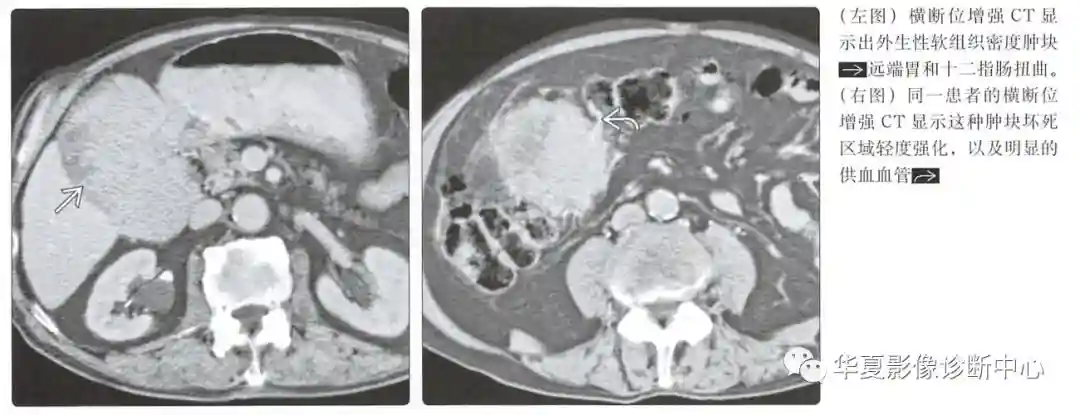

可变;大肿块可能5cm

体积庞大、界限清晰、分叶状

通常是外生的,可能有囊性成分

动脉期图像呈低或高血供,边界清楚的黏膜下肿块;溃疡和坏死是常见的

有助于观察肿块的大小和起源